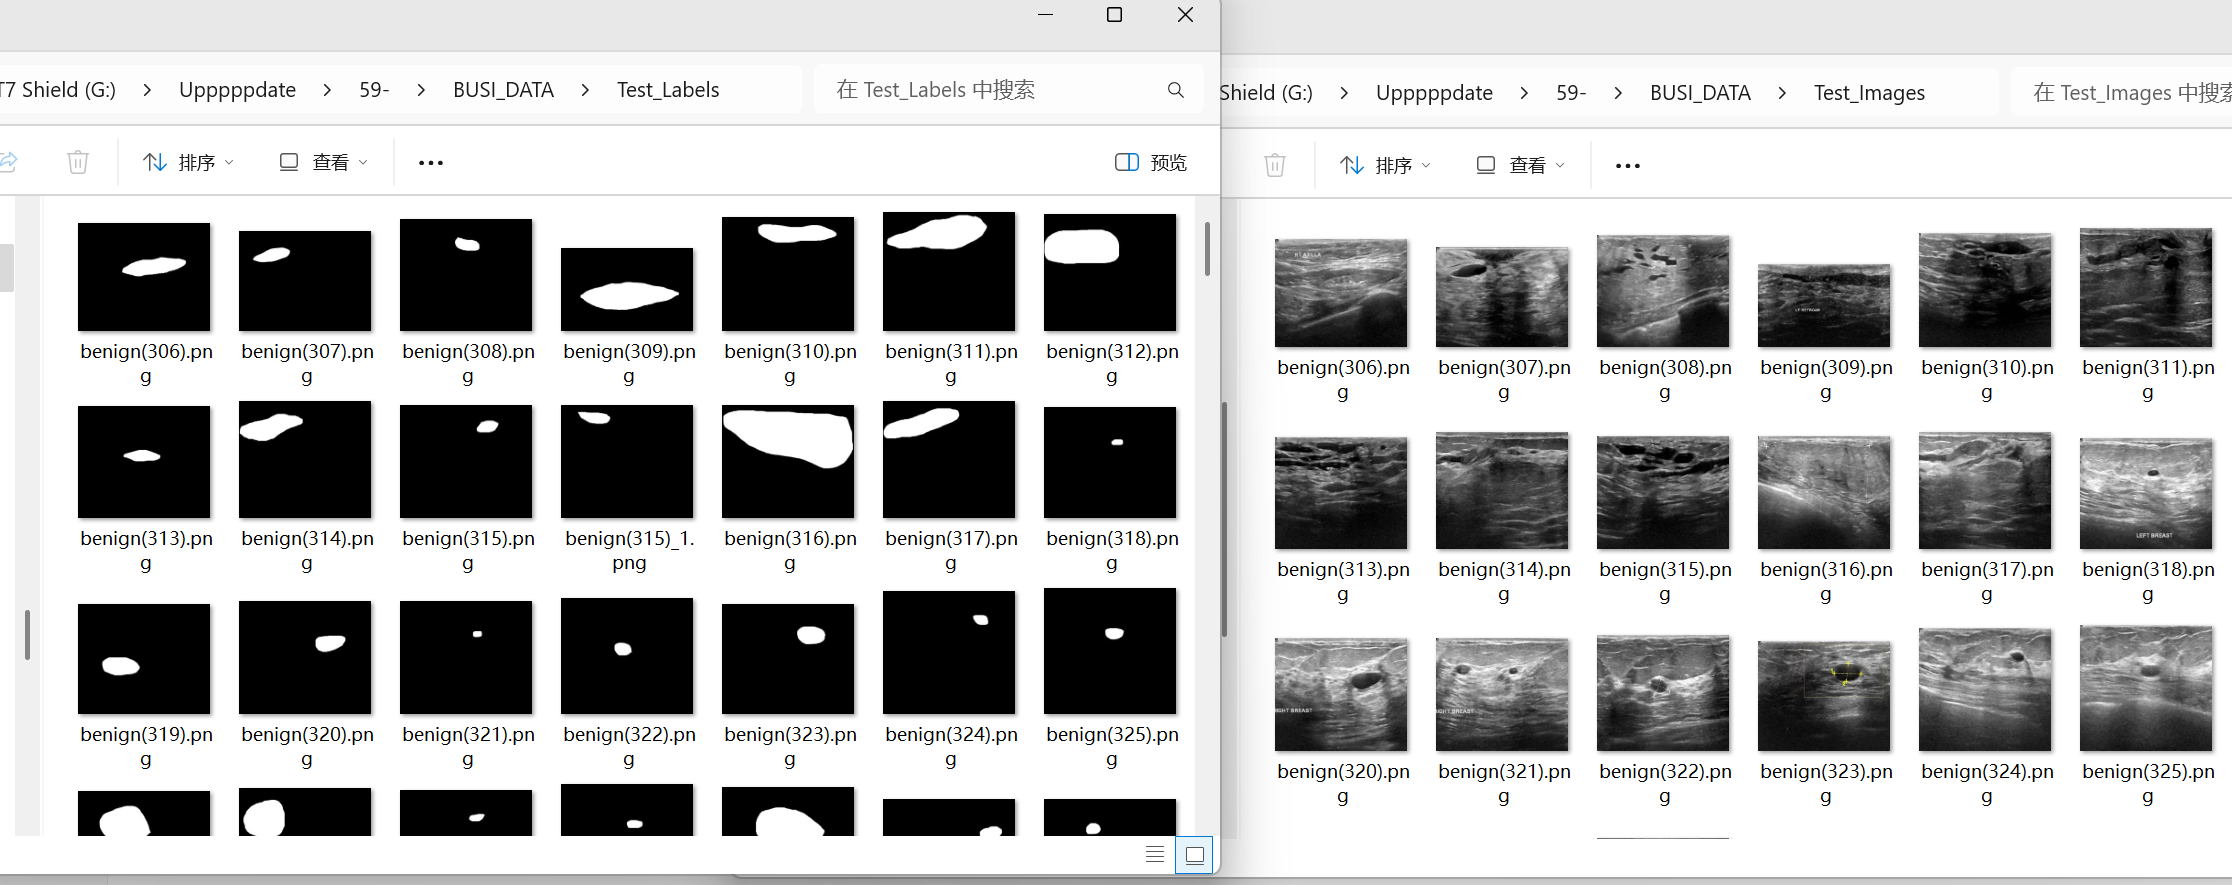

数据集分为训练集和测试集,如下图所示,分别是他们的原始图像和对应的标签文件。

对于图像和标签,一定要注意他们的名称保持一致,只要他们的名称保持一致,后面会省去很多不必要的麻烦。